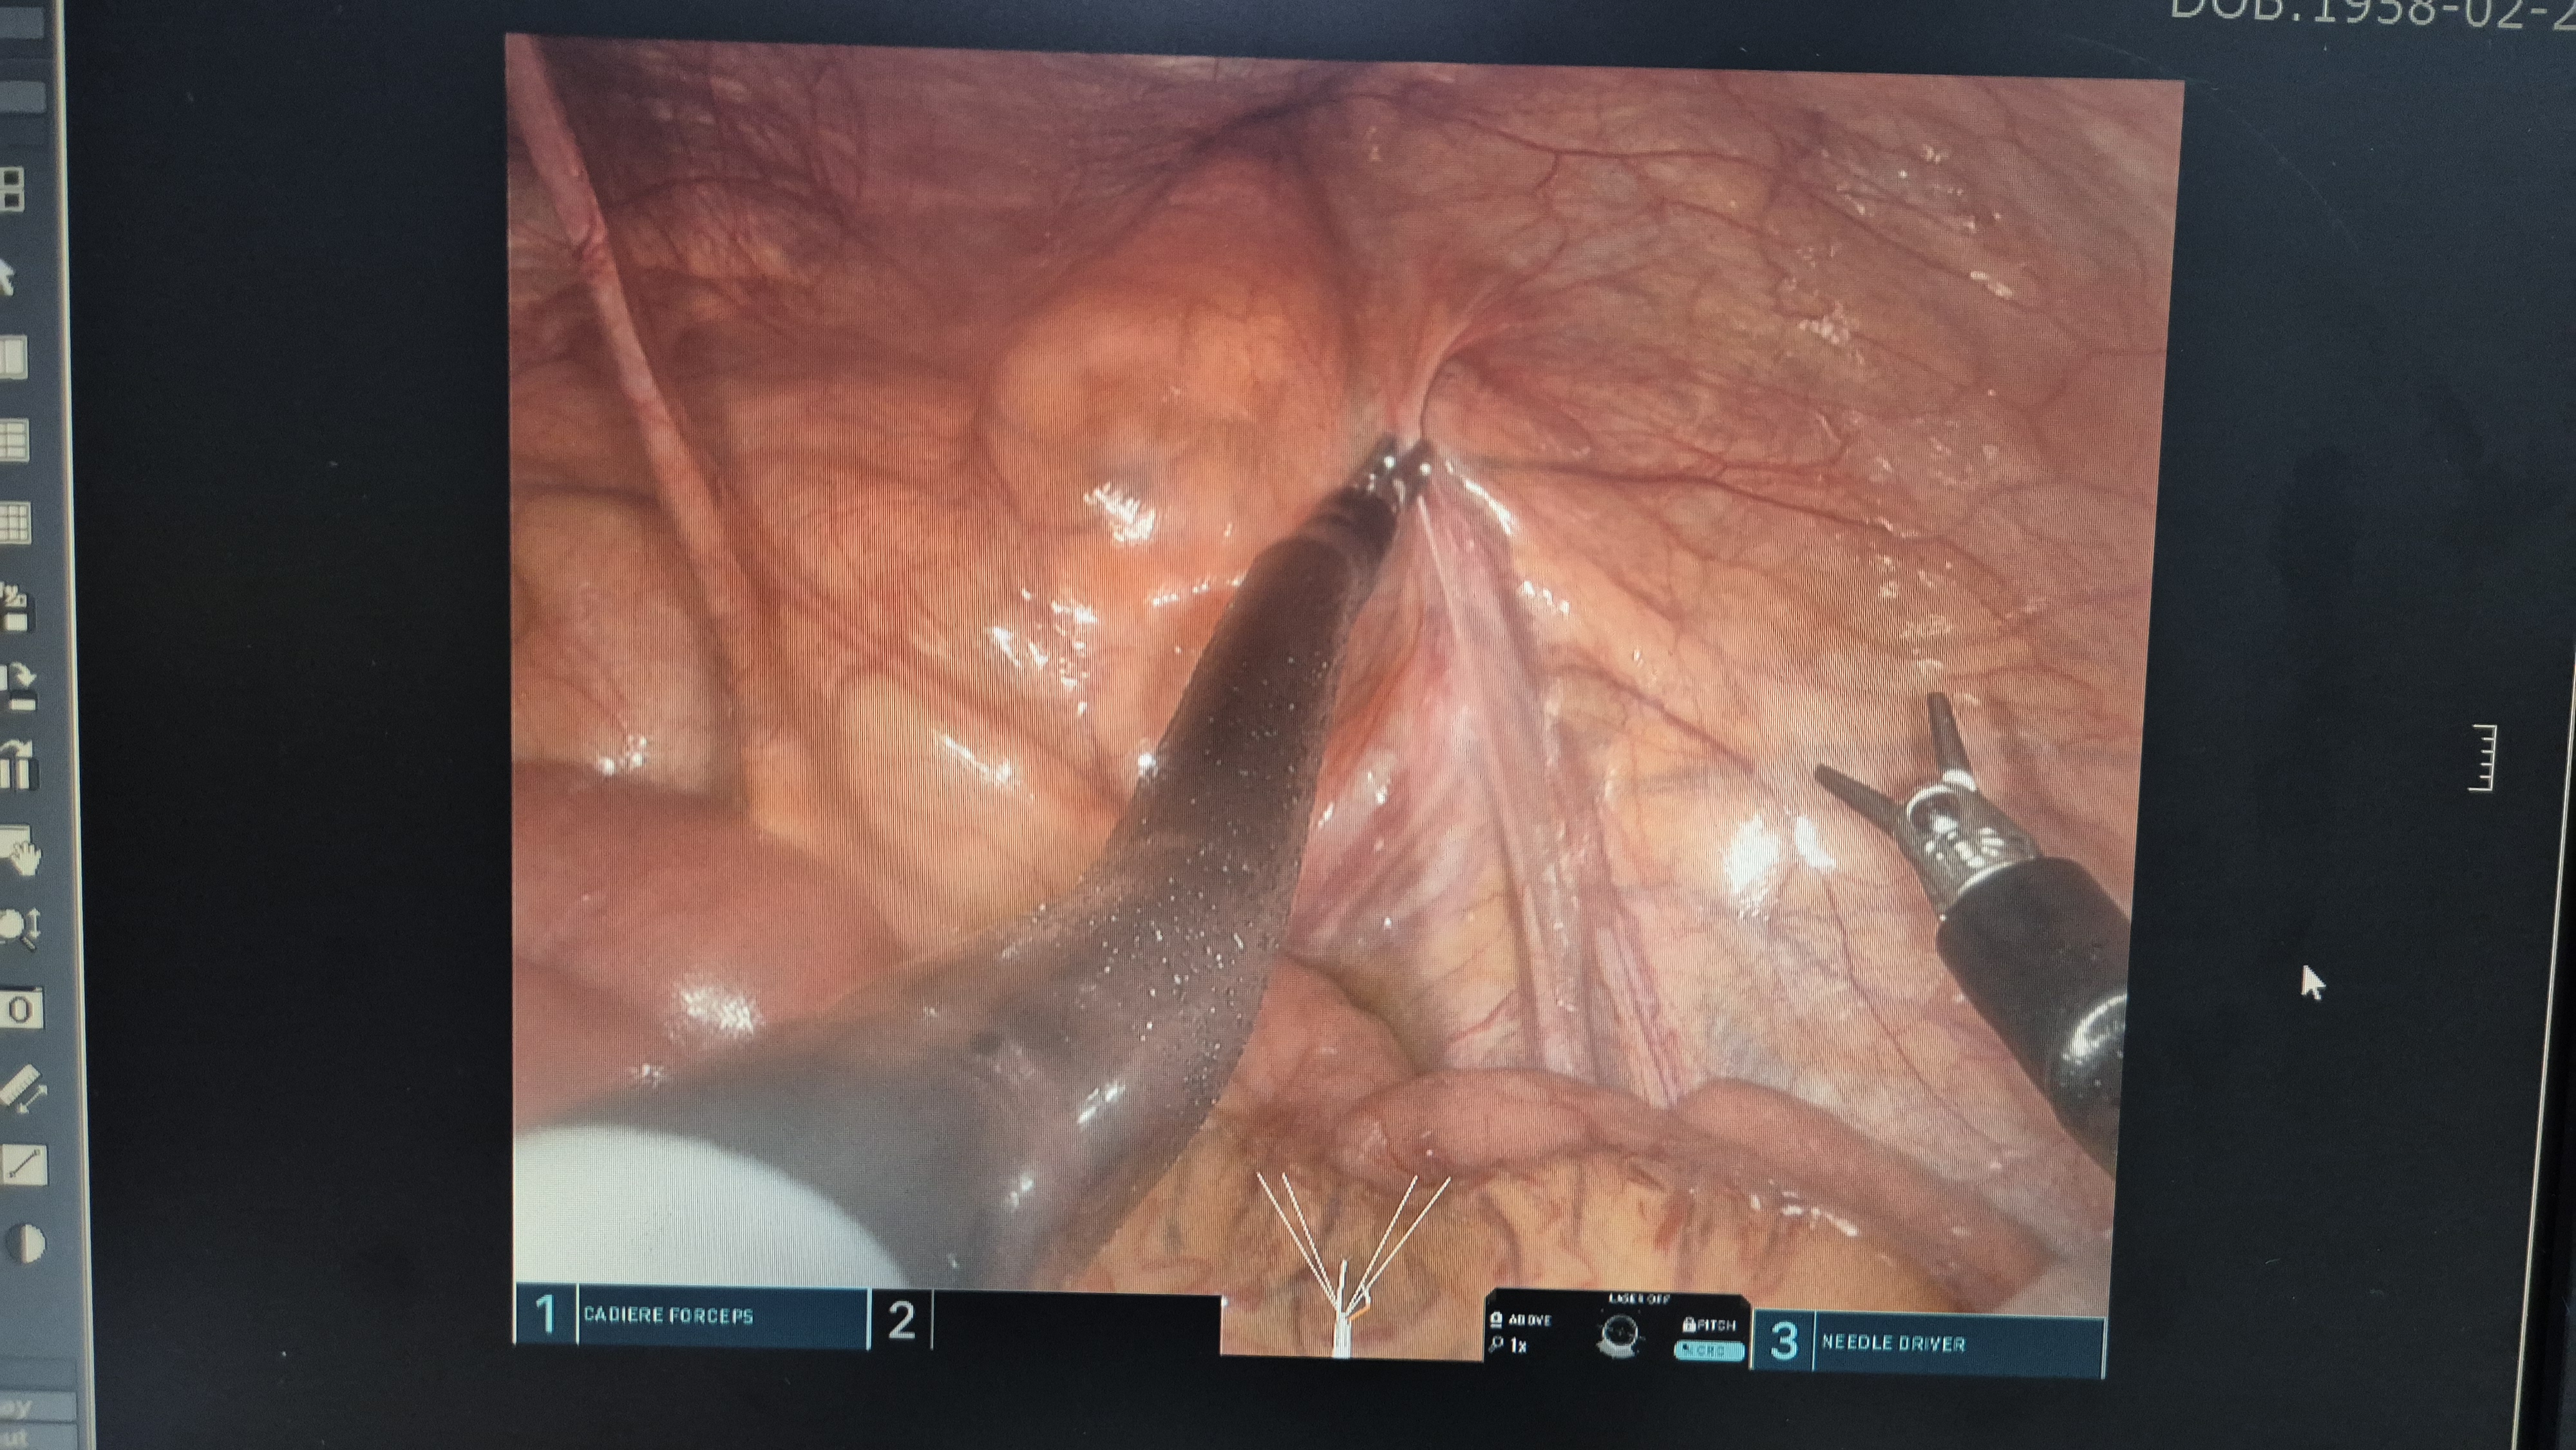

복막 봉합.

복막봉합.